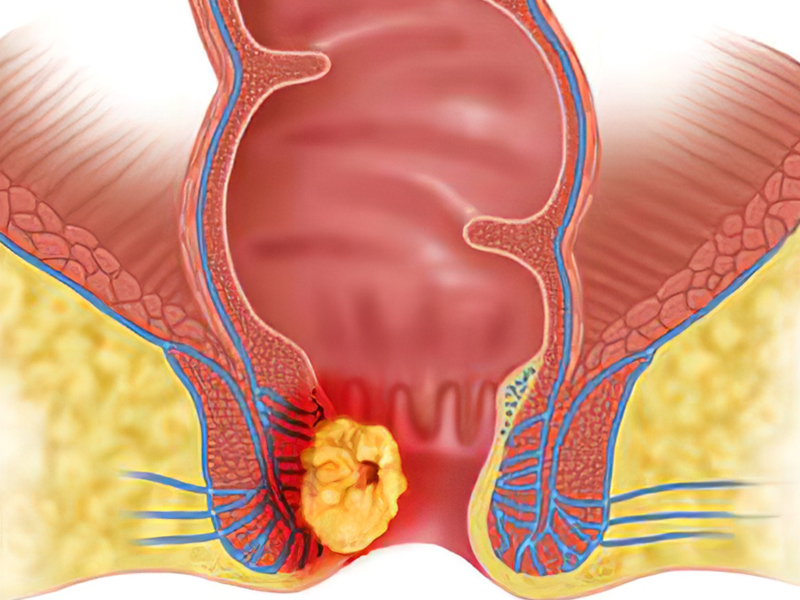

| 肛門癌屬於下消化道癌症的一種,經常發生在肛門周圍的區域,特別是齒線下方。多種因素可以誘發肛門癌,包括肛瘺、痔瘡、濕疣以及手術等對肛門造成長期慢性刺激,最終可能演變成癌症。 身體出現下列異常,警惕是肛門癌 以下是一些可能暗示肛門癌存在的症狀,如果出現以下情況,應格外警惕: 1. 大便習慣改變 排便次數明顯增多,感覺總是未排乾淨,這種情況不應輕視,不要誤以為只是普通的消化問題。 2. 糞便形狀改變 正常情況下,大便通常呈條狀,如果發現糞便變細、變形,尤其伴有黏液或膿血,應引起警惕。 3. 肛門疼痛 肛門疼痛是肛門癌的典型症狀之一,一開始可能不太明顯,但隨着病情的發展,疼痛感會加重,尤其在排便後,並且持續時間也會延長。 4. 肛門瘙癢伴有分泌物 肛門瘙癢伴隨分泌物排出,常伴有腥臭味,這也是肛門癌可能存在的症狀之一。 如果出現上述症狀,尤其是多種症狀同時存在,建議儘早諮詢醫生,進行相關檢查以排除或確認肛門癌的可能性。早期發現和治療可以提高治癒率和生存率。 肛門癌與痔瘡,別傻傻分不清 由於肛門癌並不常見,很多人即使發現異常,也容易誤以為是痔瘡,從而延誤治療。以下是一些區分肛門癌和痔瘡的方法,要特別留意,以便及早診斷。 1. 便血顏色 肛門癌引起的出血通常是暗紅色,而內痔引起的出血則多是鮮紅色。 2. 出血形式 肛門癌的出血通常是混有黏液的渾濁血液,而且出血的時間不固定;而痔瘡引起的出血通常是點滴狀或者噴射狀,血液相對較乾淨,大多在排便時出血。 3. 發作時間 痔瘡的症狀通常是間斷髮作的,休息或藥物治療可以緩解,而肛門癌的症狀是持續性的,不容易緩解。 4. 伴隨症狀 肛門癌可能伴隨全身症狀,如乏力、腹股溝淋巴結腫大等,而痔瘡一般不會引起這些全身症狀。 在面對便血或其他與肛門相關的症狀時,如果存在疑慮,應儘早就醫,並儘量尋求專科醫生的建議,以便進行全面的檢查和確診。及早發現和治療肛門癌可以顯著提高治癒率和生存率。 |